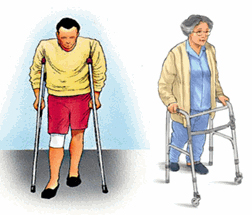

4. อุปกรณ์ช่วยในการเดิน

- การใช้ไม้เท้าเพื่อช่วยลดแรงกระทำต่อข้อเข่า ในกรณีที่ปวดมากควรถือไม้เท้าในมือด้านตรงข้ามกับข้างที่ปวดเข่า

- สนับเข่าเพื่อกระชับลูกสะบ้า ช่วยปรับความตึงของเอ็นรอบสะบ้า

รูปภาพแสดง อุปกรณ์ช่วยในการเดิน